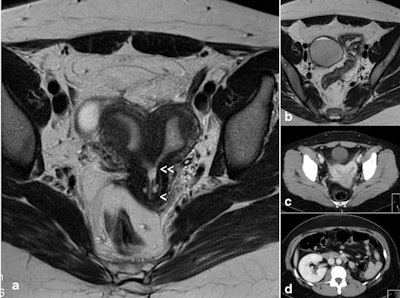

The combination of uterine duplicity and obstructed or blind hemivagina appears to be virtually always associated with ipsilateral renal agenesis or dysgenesis, and imaging tests are necessary to confirm the absence of a normal kidney on the affected side and also to detect abnormalities of the contralateral kidney and ureter, they added.

If there is unilateral renal agenesis, there must also be genital malformation with didelphys, bicornuate, and, more rarely, septate uterus (sometimes reported as single uterus), but not necessarily a blind or atretic hemivagina. There could also be cases with partial reabsorption of the vaginal septum, they continued.

Differentiating between a bicornuate and a septate uterus also is controversial. The distinction is important for the treatment of symptomatic patients (abdominal Strassmann metroplasty on the bicornuate uterus versus hysteroscopic resection in cases of septate). Transvaginal ultrasound, 3D ultrasound, sonohysterography, and especially MRI have ushered in a new era of noninvasive diagnosis of uterine anomalies.